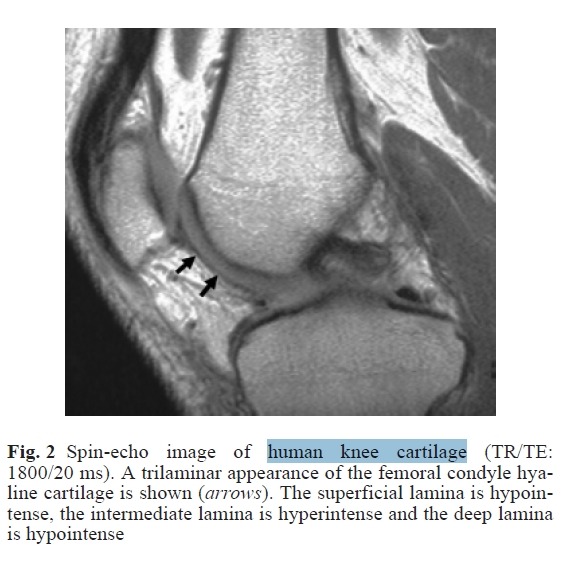

hyaline cartilage의 퇴행화 과정에서 보이는 MRI 영상

Cartilage degenerative diseases, such as osteoarthritis, affect million of people. Magnetic resonance imaging is presently the most accurate imaging modality in eval‎uating the state of hyaline cartilage; however, clinical MRI does not accurately reveal early degenerative alterations in cartilage, due mainly to low spatial resolution.

Magnetic resonance microscopy (MRM, or μMRI) appears exceptionally well suited to the in vitro or ex vivo study

of this heterogeneous tissue, due to its high spatial resolution; however, despite this, further studies are necessary

to eval‎uate the potential of MRM in the detection of early cartilage damage.

Herein we briefly review the current applications of MRM in the study of hyaline cartilage. In particular, we review the

MR appearance of hyaline cartilage on high-resolution images, the different MRM techniques used to image normal and enzymatically or chemically degraded cartilage and the potential use of contrast agents.

The future directions and the relevance of MRM findings for a better understanding of cartilage physiology in health and disease are also discussed.